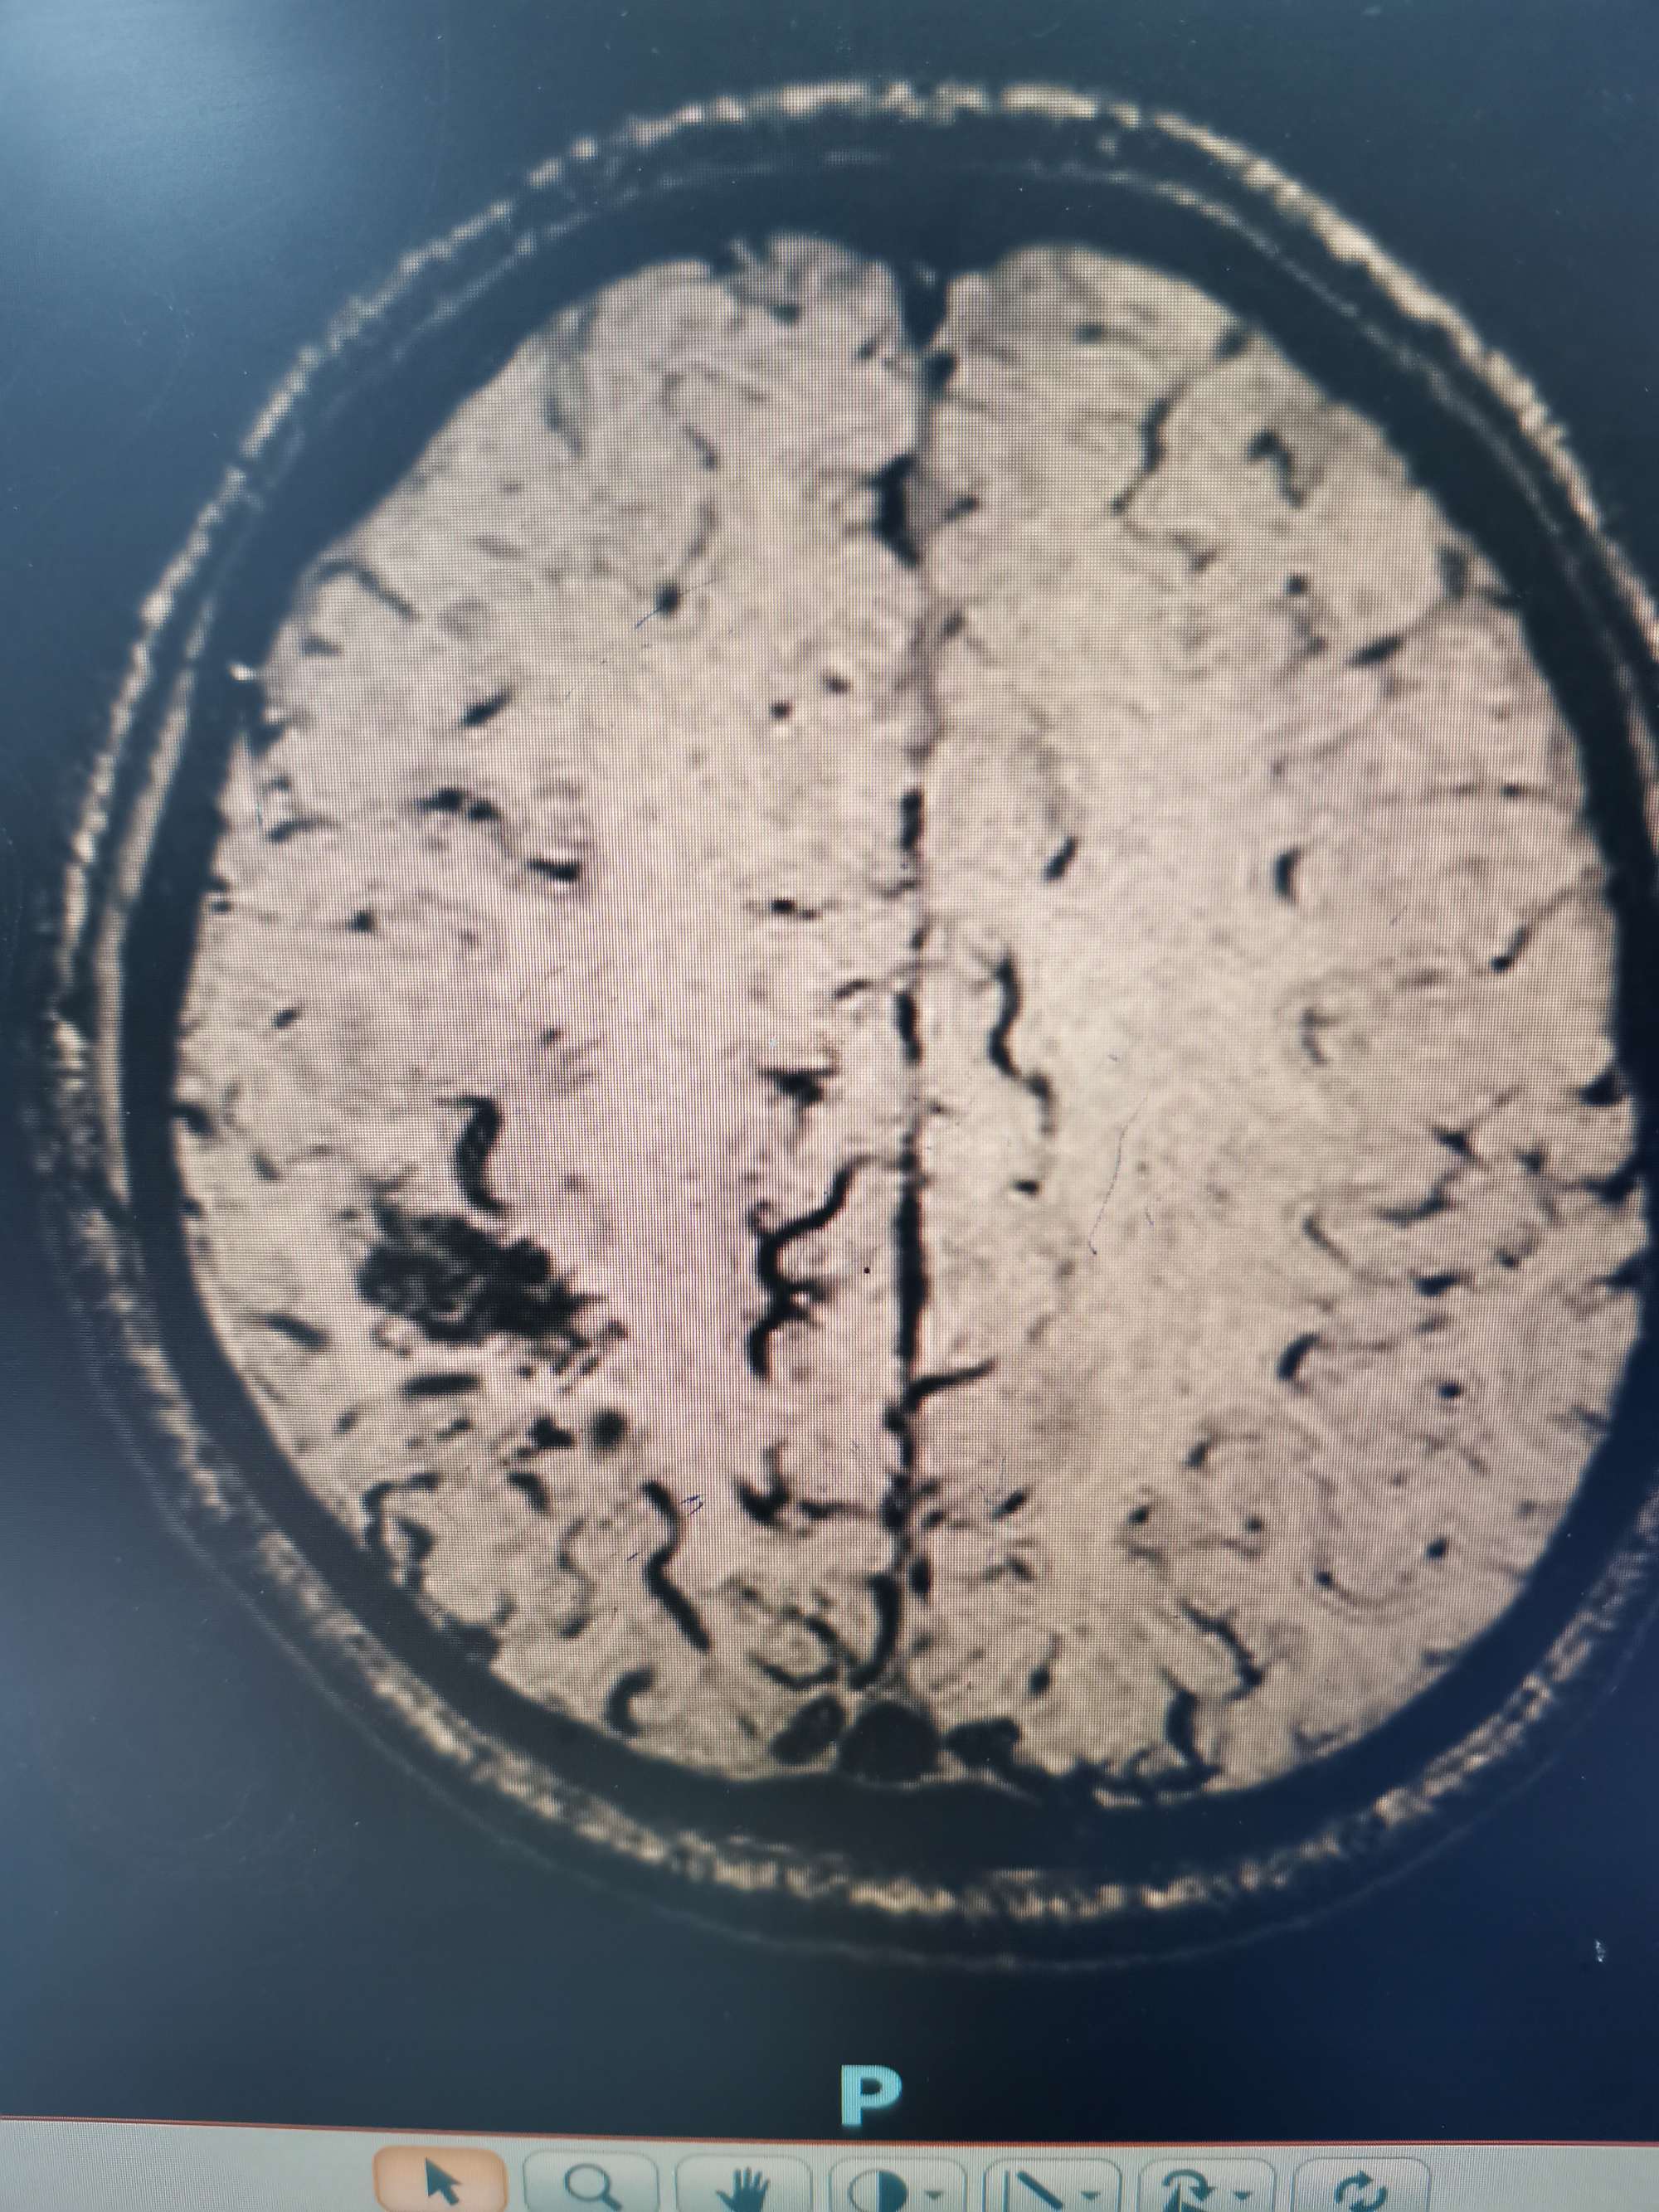

外院磁共振提示右侧顶叶病变

入院后急查头颅磁共振发现顶叶又新发两个病灶。

磁共振发现顶叶又新发两个病灶

DWI考虑新发病灶为脑梗死,考虑该梗塞病灶位于运动皮层导致患者右下肢完全偏瘫。

磁敏感成像考虑首发病灶为出血。